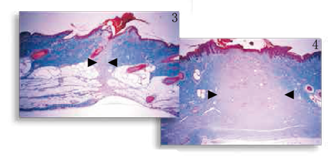

圖3,4

傷口愈合改進 觀察豬皮皮膚切口的縮影(圖3 )與標(biāo)準(zhǔn)的尖端切口(圖4 ),經(jīng)由梅森氏三色染色顯示纖維增生明顯減少,如膠原沉積的程度和炎癥反應(yīng)。